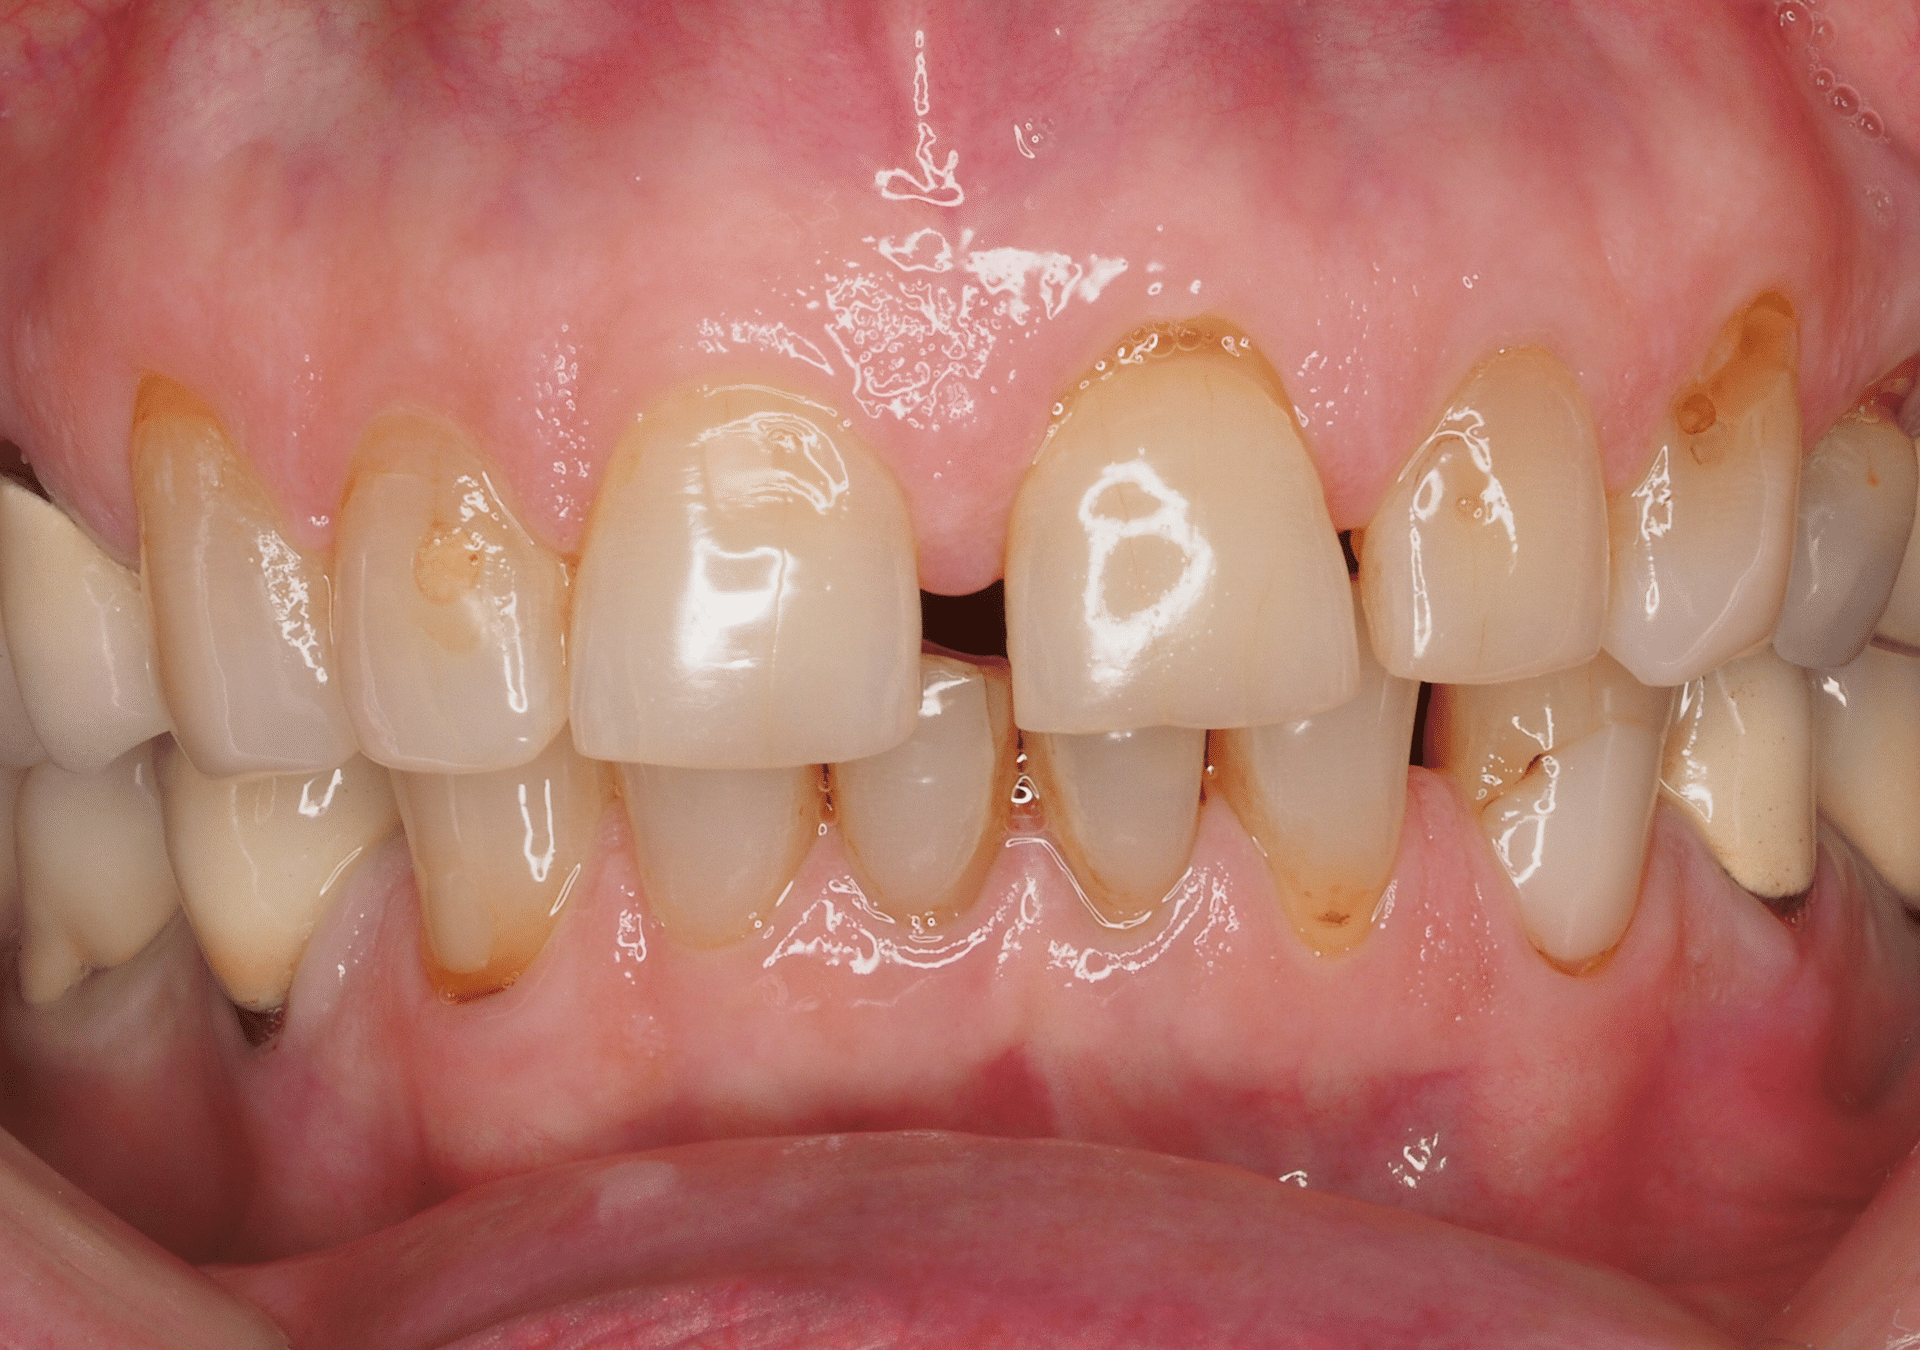

- Protocolo del doctor Josep Lluís Padrós actualizado con aplicación mixta domicilio/clínica, con resultados exitosos el 100% de los casos.

- Técnicas de blanqueamiento eficaces en casos difíciles, incluidas las tinciones por tetraciclinas.

- Tratamiento confortable y de gran durabilidad, sin alterar la estructura dental